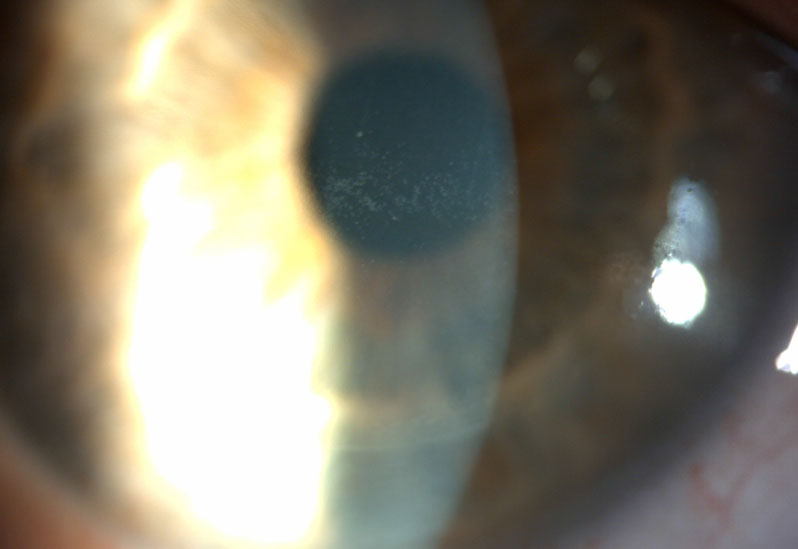

- Slit Lamp Exam